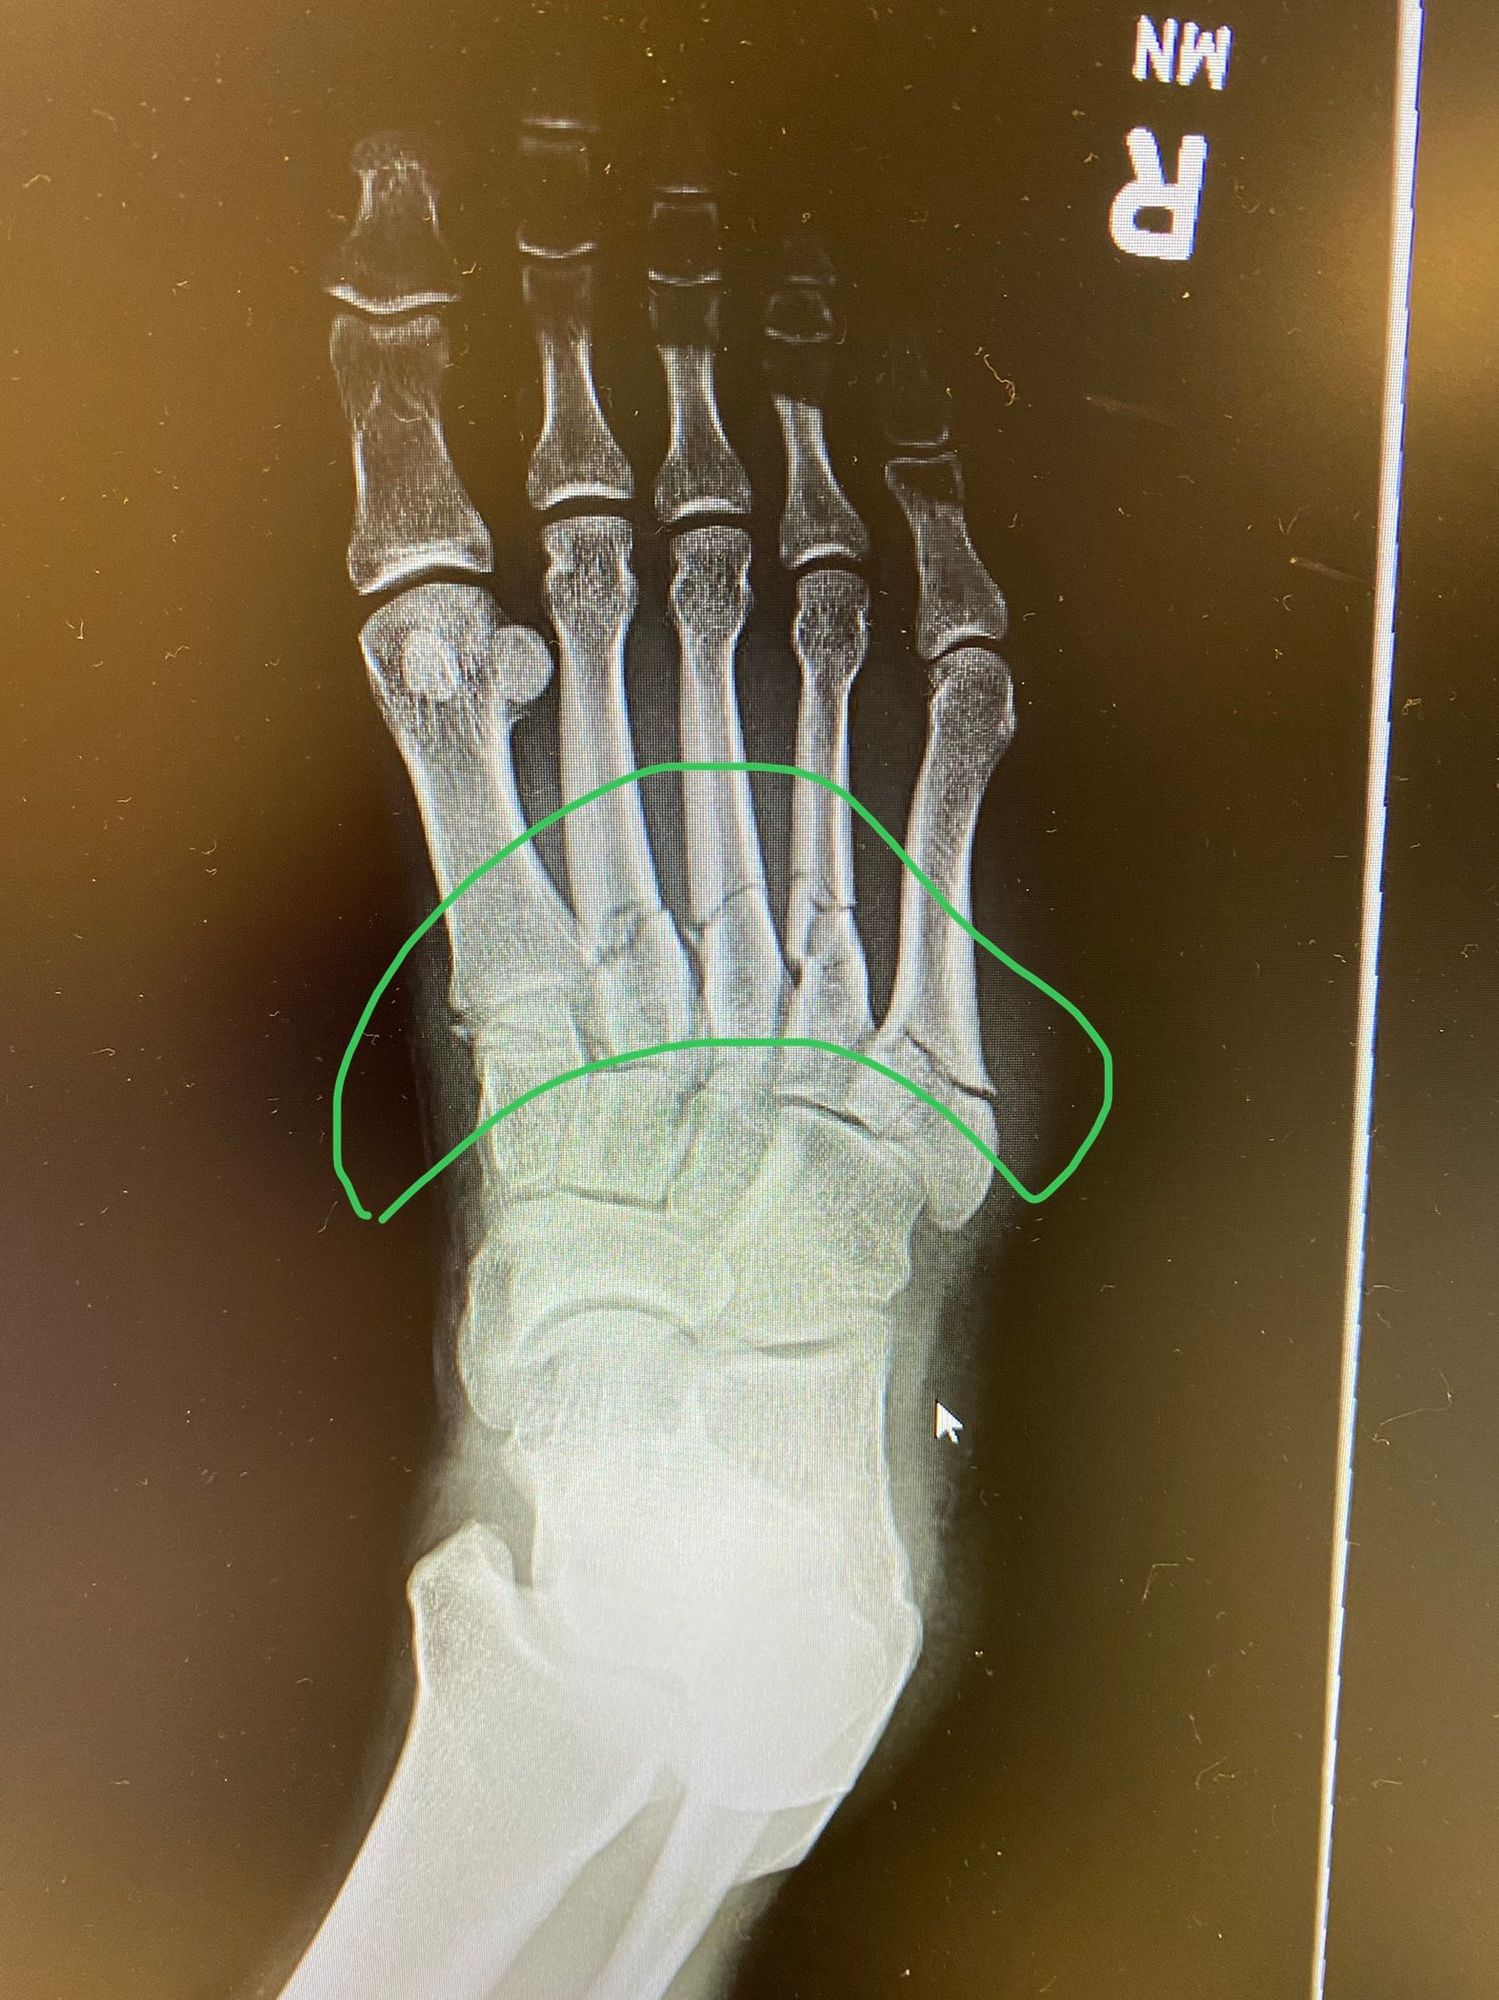

All five metatarsals broke.